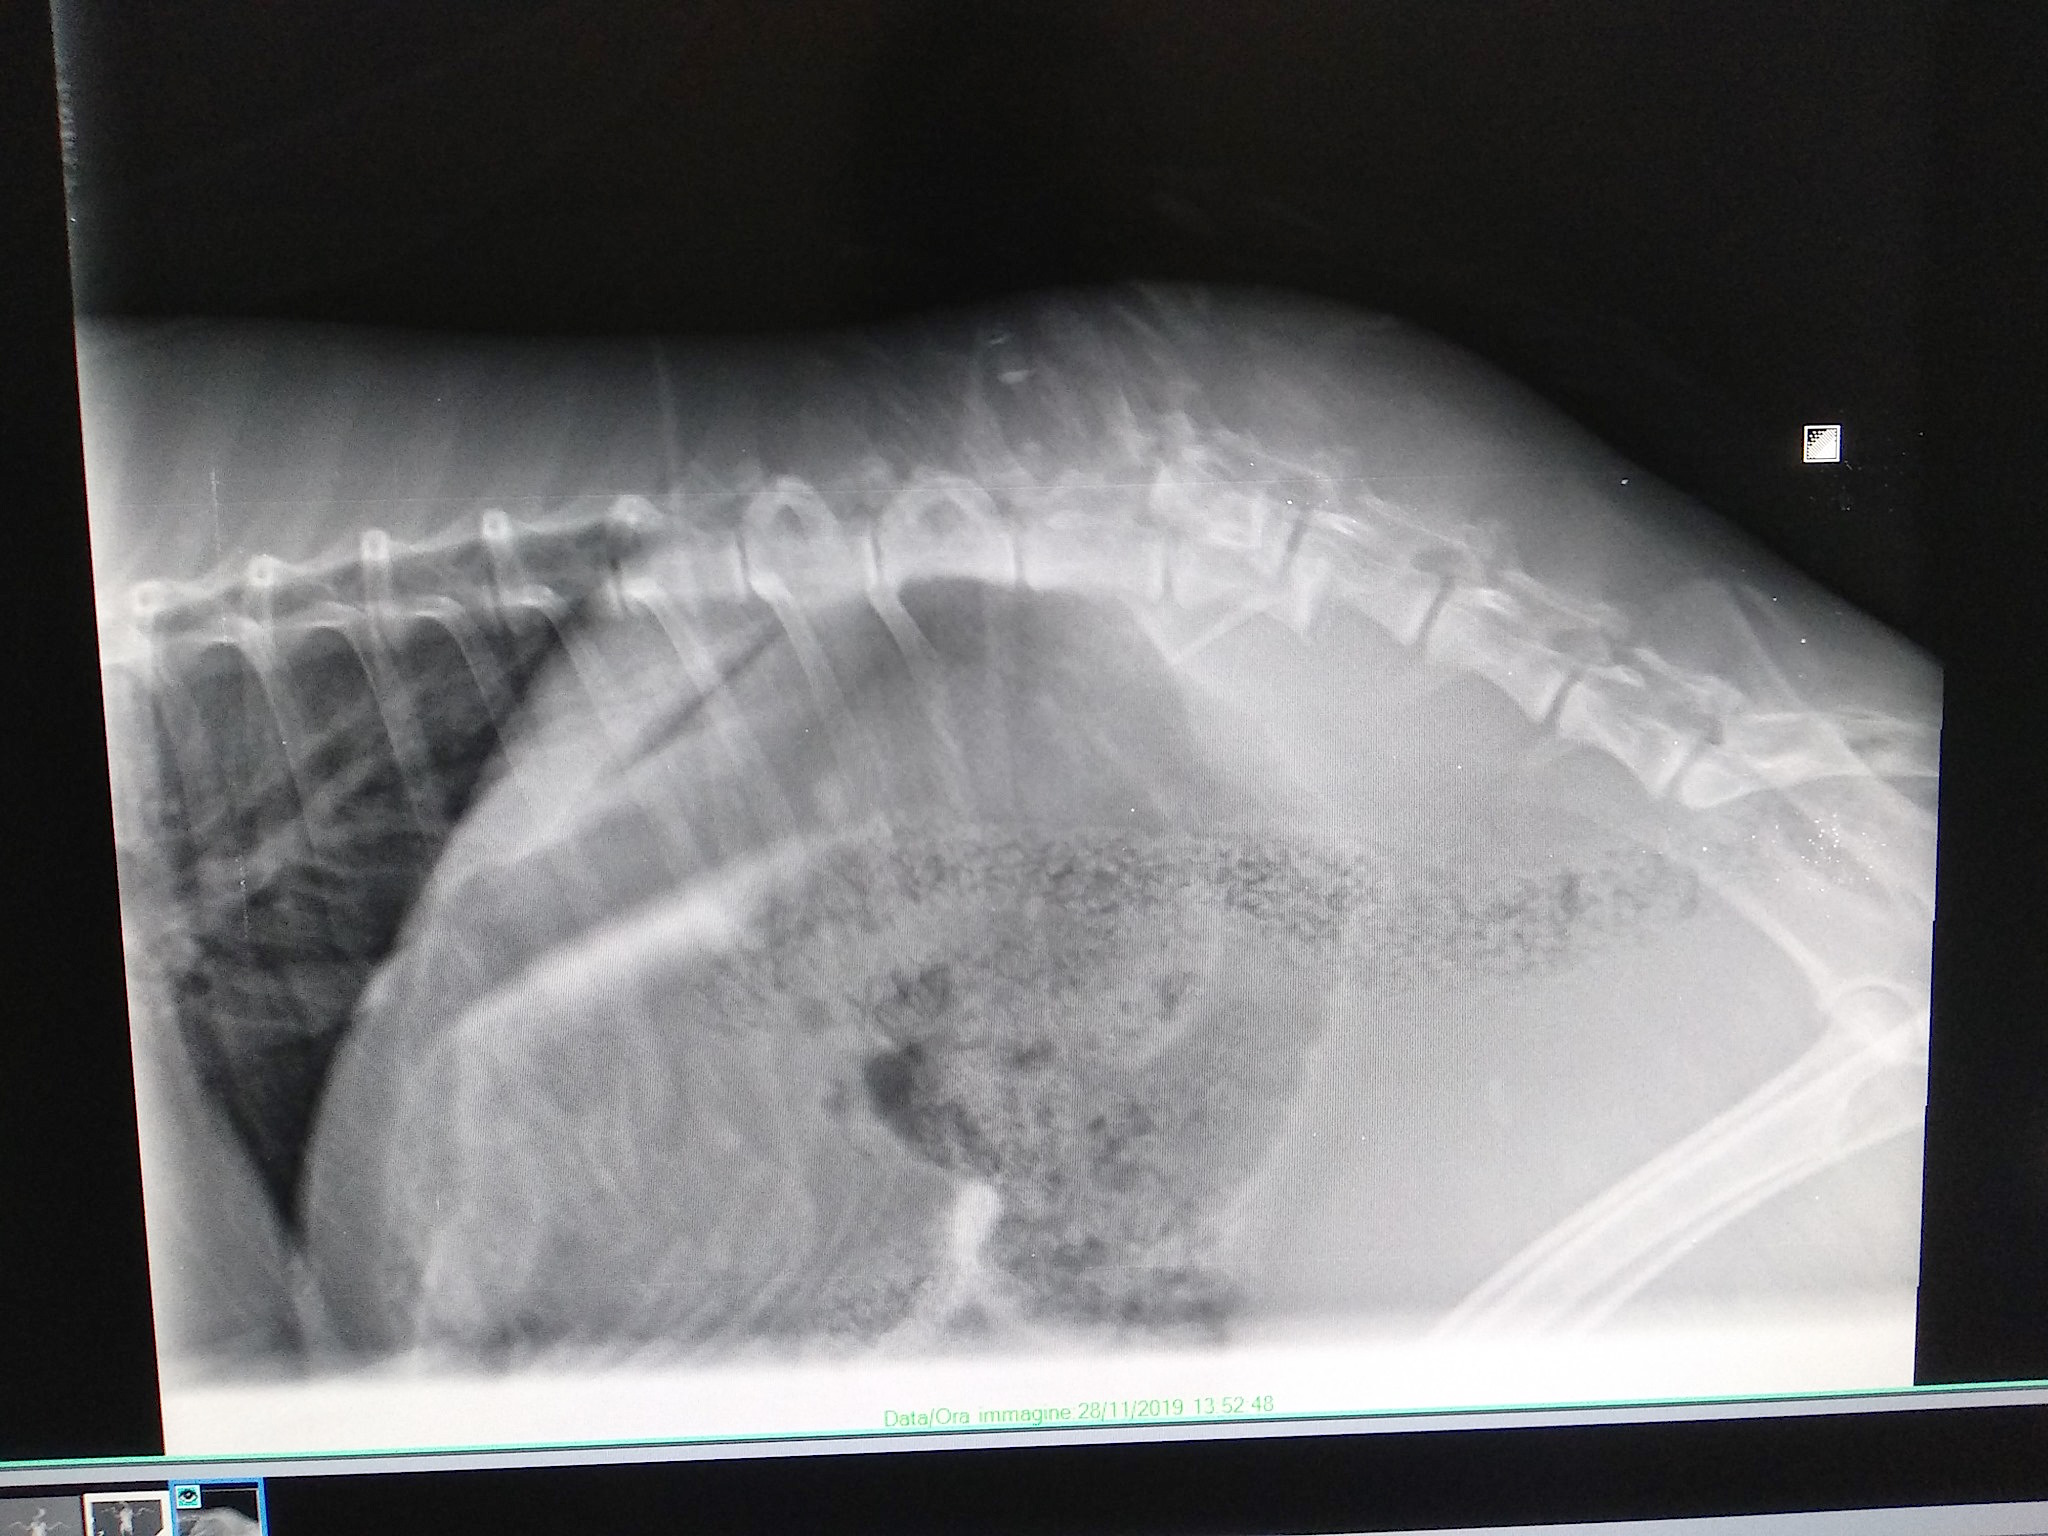

Al CRAS è stato preso in consegna dall’addetta dipendente ANPANA Erica Mascherpa, che dopo averlo messo al sicuro all’interno della struttura ha attivato il servizio veterinario. Sono bastati i raggi per evidenziare quello che era un sospetto sin da principio. Il giovane capriolo aveva una frattura scomposta della colonna vertebrale, causato dalla caduta nella canalina. Al veterinario non è restato altro da fare che addormentarlo per sempre.